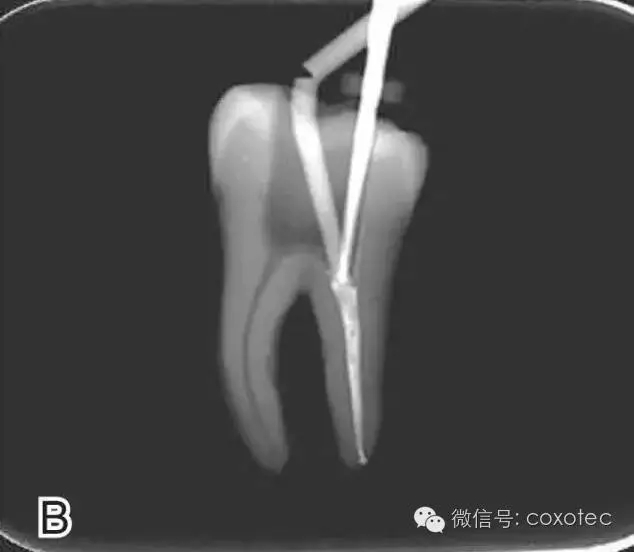

要求工作尖能自由到達(dá)距根尖4~5 mm(有學(xué)者提出3~4 mm)的位置并能輕微接觸根管壁,用橡皮片做好標(biāo)記(圖1)

圖1 選擇攜熱器工作尖,A.試攜熱器尖 B.工作尖在根內(nèi)的位置